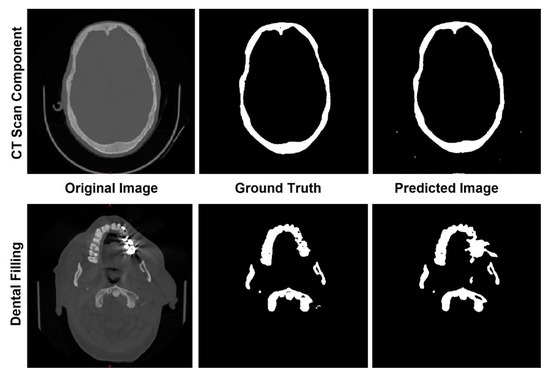

These results are close to those DSCs reported by [26] (mean DSC of 0.92), and slightly lower than the results reported by [27] (mean DSC of 0.98). Regarding HD, its discrepant values may be directly related to segmentation errors due to bright artifacts found in the original image, which may be caused by dental filling and components of the CT scan machine, as shown in Figure 3. However, any necessary modification was performed by manual corrections after the segmentation. These predicted labels play an important role in the coronal and transverse alignment.

Figure 3.

Errors in the predicted images caused by machine components and dental fillings.